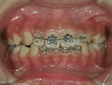

| 全体の矯正が必要ですね。 |  | 奥歯にゴムを挟んで 歯と歯の間を広げます。 |  | バンドが入りましたよ。 |  | きちんと磨けるように 歯ブラシ指導をします。 |  | 矯正器具(ブラケット)を取り付けます。 |  | 最初のワイヤーが入りました。 少しずつ歯が動き始めますよ。 |  | 計画に従って歯を動かしていきます。 調整はおよそひと月に1度です。 |  | 前歯も奥歯もきちんと治りましたね。 装置を取り外します。 |  | 保定装置をはめて メインテナンスをします。 |

| (これから矯正を始める患者さんの為、当クリニックで治療を終えた患者さんのご好意で写真を掲載させていただいています) |